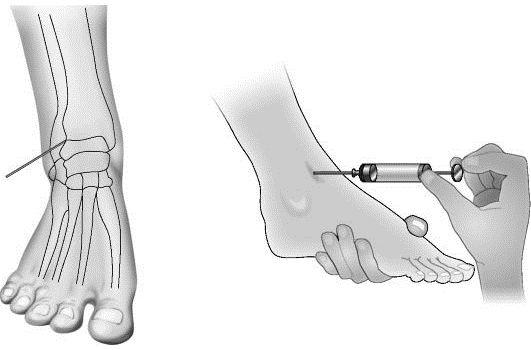

Рекомендуется использовать специальные ортопедические стельки. При инфекционном воспалении назначаются противомикробные средства, включая антибиотики и противовирусные препараты. Полезно также принимать витамины. В тяжелых случаях могут быть проведены инъекции в полость голеностопного сустава. В терапию часто включаются системные кортикостероиды.

Иногда проводится лечебная пункция для аспирации содержимого. В полость сустава может вводиться антибиотик. При лечении ревматоидного артрита предпочтительными являются кортикостероиды, цитостатики, иммунодепрессанты и инактиваторы фактора некроза опухоли. При подагре следует исключить мясные продукты из рациона и назначается Аллопуринол.